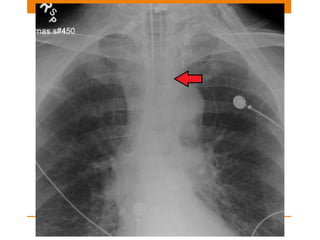

Pacemaker

SINGLE OR DUAL CHAMBER

Single chamber –nowadays used less frequently

• used for atrial or ventricular dysarrythmia

• Atrial – positioned in right atrial appendage

• Ventricular – Electrode placed against myocardium at

apex of right ventricle

Dual pacemaker

• Attempts to synchronize atrial and ventricular system

• One electrode @ Right atrium

• Other electrode @ apex of right ventricle

Sometimes a third lead is also noted

• Third –coronary sinus <Biventricular pacing>

Pacemaker SINGLE OR DUALCHAMBER Single chamber –nowadays used less frequently • used for atrial or ventricular dysarrythmia • Atrial – positioned in right atrial appendage • Ventricular – Electrode placed against myocardium at apex of right ventricle

Pacemaker Dual pacemaker • Attemptsto synchronize atrial and ventricular system • One electrode @ Right atrium • Other electrode @ apex of right ventricle Sometimes a third lead is also noted • Third –coronary sinus <Biventricular pacing>